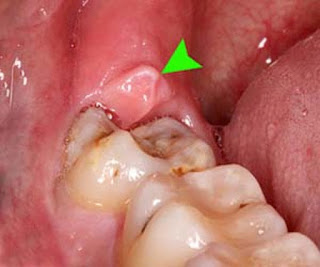

Όταν ένας φρονιμίτης της κάτω γνάθου δεν έχει ανατείλει καλά, είναι ημιέγκλειστος όπως λέμε, καλύπτεται μερικώς από ούλα, την καλύπτρα.

Η καλύπτρα εμποδίζει την καλή στοματική υγιεινή, υπολείμματα τροφών συσσωρεύονται εκεί και μικρόβια αναπτύσσονται. Μερικές φορές ο από πάνω φρονιμίτης μπορεί να προκαλεί τραυματισμό κατά τη μάσηση. Σαν συνέπεια προκαλείται φλεγμονή της περιοχής που ονομάζεται περιστεφανίτιδα.

| Ουλική καλύπτρα |